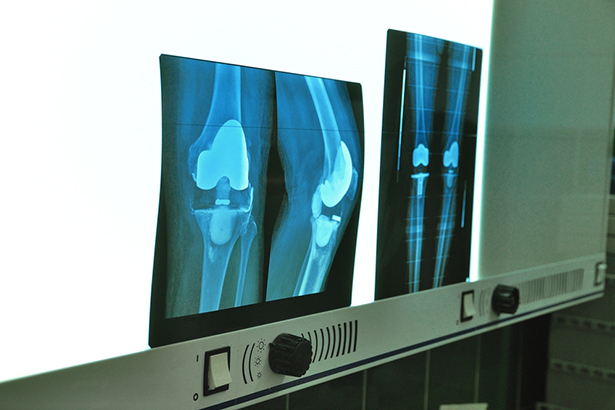

Gezocht:kunstknie zonder servicecontract

Fabrikanten van medische implantaten helpen dagelijks mee bij operaties. Wat Nederlandse ziekenhuizen exact betalen voor die service is in nevelen gehuld, zelfs voor zorgverzekeraars. Medische implantaten zijn (onder andere daardoor) duur. Over de grens zijn ze vaak goedkoper te krijgen, maar de implantaten daar inkopen lukt meestal niet: ziekenhuisinkopers stuiten op handelsbarrières van de industrie. “We zijn machteloos.”

Afgelopen jaar brachten Argos en Small Stream Media aan het licht dat vertegenwoordigers van fabrikanten regelmatig in de operatiekamer assisteren bij het plaatsen van implantaten. Uit vervolgonderzoek in samenwerking met Follow the Money blijkt nu dat de ziekenhuiskosten worden opgedreven door deze medische verkopers. Ondersteuning op de Operatie Kamer (OK) is een wapen van de industrie om implantaten duurder aan de man te brengen. Via de ondersteuning aan artsen wordt, onder het mom van patiëntveiligheid, druk uitgeoefend op ziekenhuizen om de implantaten tegen de relatief hoge Nederlandse tarieven aan te schaffen. Veel implantaten zijn in Duitsland een stuk goedkoper. Maar inkopers die over de grens spullen willen inkopen, ondervinden op meerdere fronten weerstand.